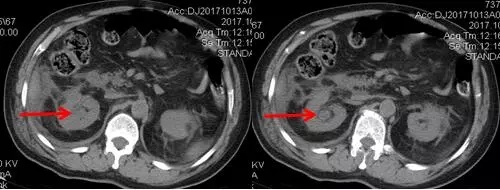

術后CT,箭頭所指為腎結石被徹底清除

三日后,曾奶奶病情逐漸穩(wěn)定,各項感染指標逐漸恢復正常,復查CT顯示腎結石已經被完全清除,現(xiàn)已康復出院。就此,困擾曾奶奶多年,反復感染差點致命的腎結石頑疾被徹底治愈。曾奶奶全家人對于愛康醫(yī)院泌尿外科專家高超的碎石取石手術技藝更是贊許有加,對泌尿外科團隊的工作給予衷心感謝和高度評價。